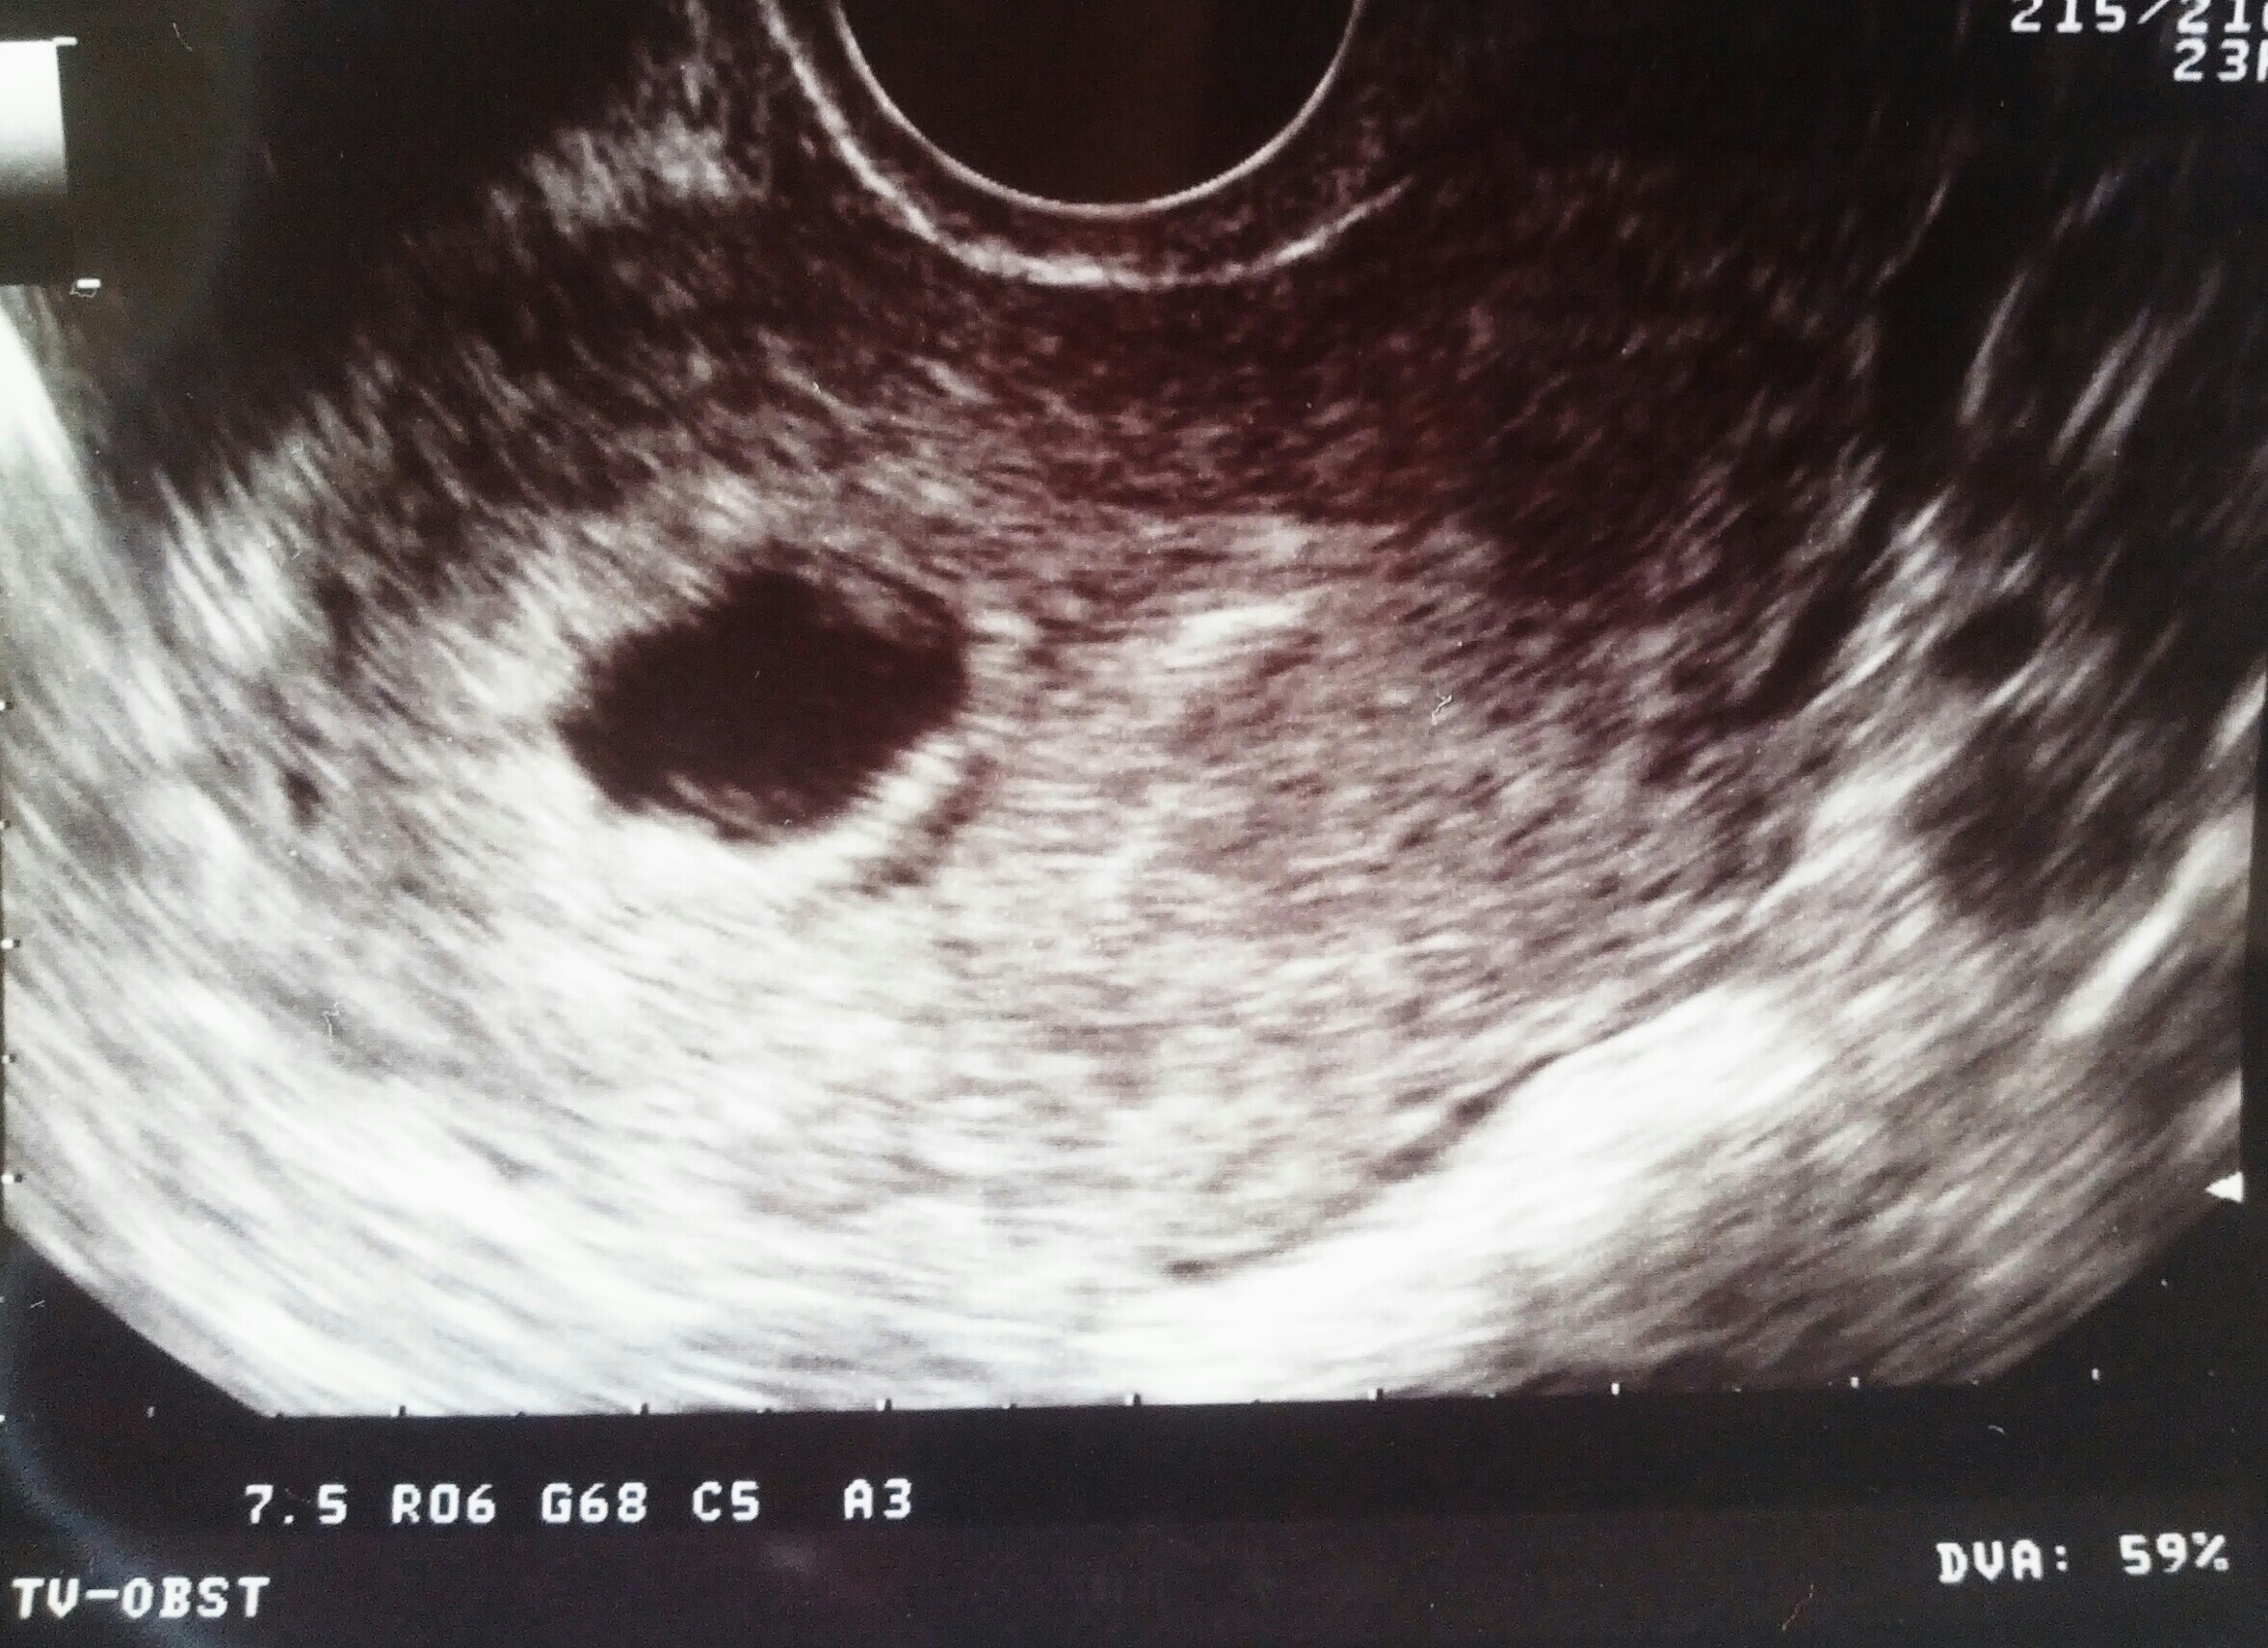

Hi ladies, had a scan today at 6 weeks

Scan: transvaginal

Plane: sagital

Orientation: my right side is on the right and my left side is on the left of the picture.

Any one who is comfortable to help explain your guess.